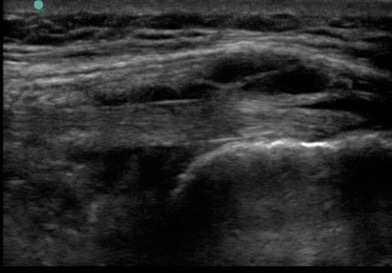

Knee Long Axis Pes Bursitis Image